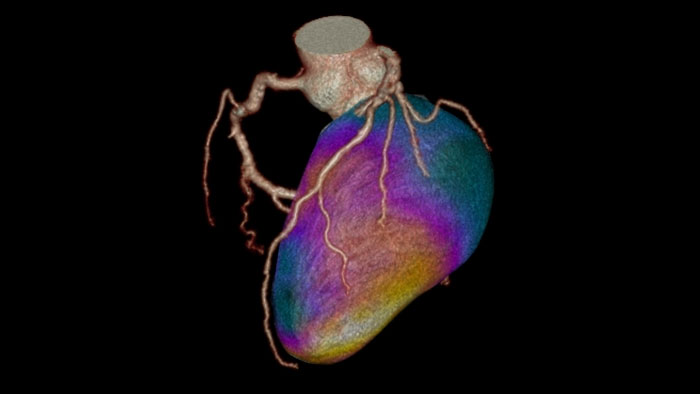

Evaluate fused coronary anatomy

Emory Cardiac Toolbox (ECTb) HeartFusion offers fusion of a patient’s coronary tree from cardiac CT angiography with MI perfusion images.